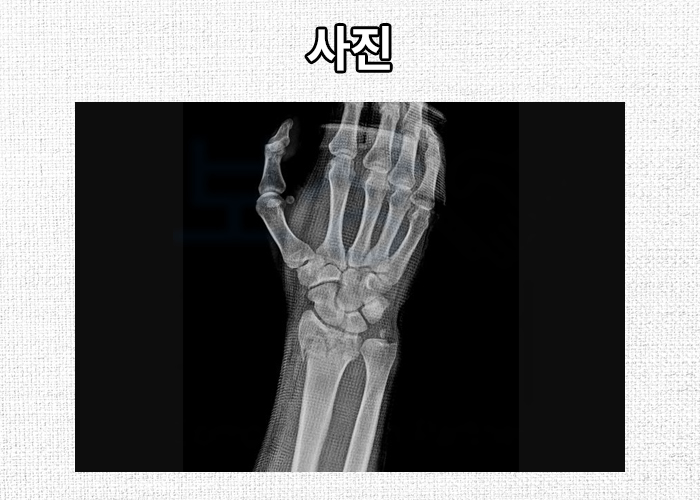

수술 전 손목의 상태입니다.

의뢰인의 진단서를 보시면 요골 및 척골 골절 진단받으신게 확인되고 금속판 고정술을 시행하셨죠. 우선 의뢰인의 보험증권을 받아 보험가입 시기, 담보, 약관 분석을 도와드렸습니다.